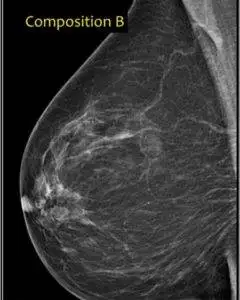

Cat. B: Sparsely spread areas of fibroglandular density.

Here, scattered areas of fibroglandular density exist but the rest of the breast remains predominantly fatty. Approximately 40% of women have breasts that fall into this category which is 4 out of every 10.

There was no way I could discuss dense breasts specifically, without showing you images. Therefore I obtained all these images from “Radiology Assistant”, of the Netherlands and I am grateful.

They were very thorough on this subject and included an exciting approach I liked, in distinguishing the categories mentioned above.

Category. B: 25-50% Fibroglandular.